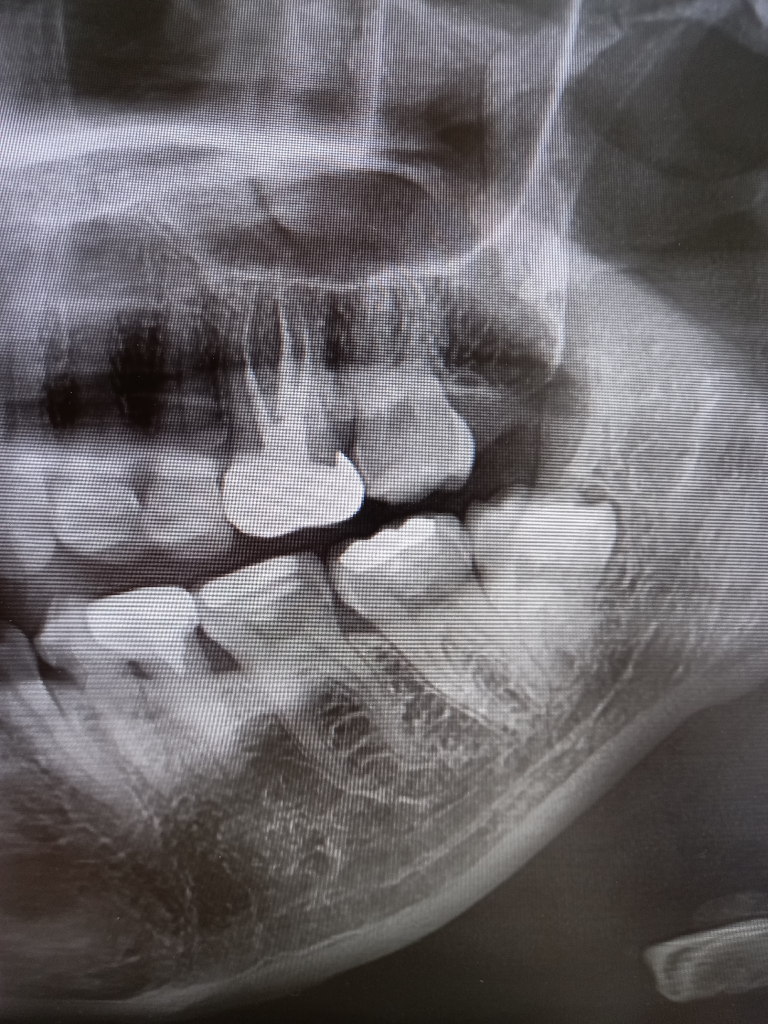

사랑니 발치 후 통증있던 어금니 괜찮을까요?

토요일부터 사랑니 옆 어금니 통증이심해(신경치료했던부분) 그 부분 입술 및 턱 마취덜풀린것처럼 감각이 이상하고 찌릿했는데요 3시간전에 사랑니발치했는데 선생님께서 사랑니때문에 어금니가 아플수도있고 아닐수도있다고하시던데 지금 마치풀리는데 어금니도 그대로아프고 일부감각이상도그대로에요..나중에 신경치료를 다시받아야하는걸카요ㅜㅜ

• 1번 째 사진